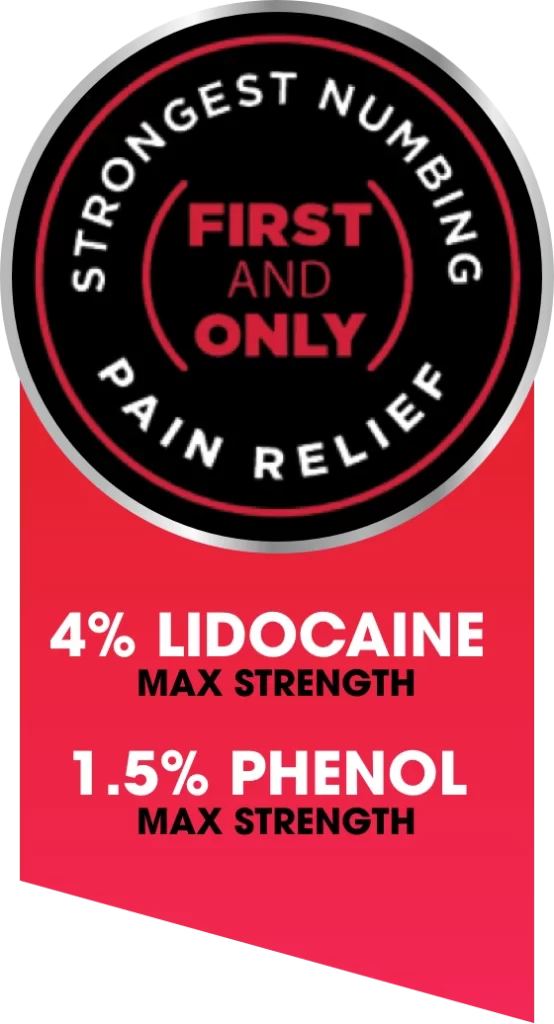

WITH 2 MAXIMUM STRENGTH ANESTHETICS

Lidocaine + Phenol

Lidocaine Works Harder with Phenol to Provide the Strongest Numbing Pain Relief on the Market*

Phenol is a numbing agent and also a penetration enhancing ingredient. “Penetration enhancers (CPE)” are proven to increase the transport of drugs across the skin layers and help Lidocaine work even harder. These two ingredients combine for the Maximum Numbing Pain Relief Available without a Prescription for long lasting and deep penetrating pain relief.

Lidocaine belongs to the family of medicines called local anesthetics. This medicine is a numbing agent that prevents pain by blocking the signals at the nerve endings in the skin. It’s deep penetrating and fast acting. 4% Lidocaine is the maximum strength available without a prescription.

Phenol helps block the channels needed to initiate and transmit pain signals and suppresses some blood flow to the affected area, which can also help to interrupt pain and inflammation cycles. And because Phenol is a penetration enhancer and readily absorbed through the skin, it helps Lidocaine start to work quicker and deeper than it could on its own.